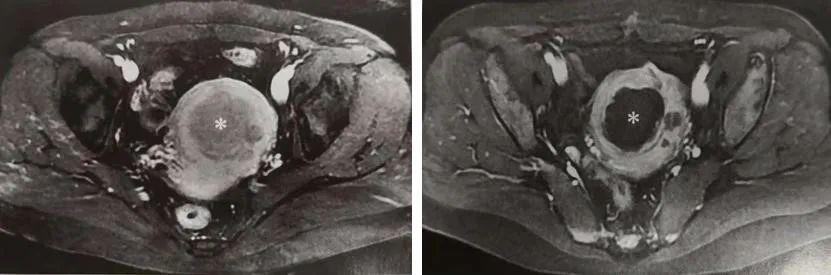

海扶刀治疗在妇科良性肿瘤治疗方面已积累了10万多病例,尤其是对于有生育要求或保留子宫的患者,海扶刀治疗具有显著优势。与传统手术相比,海扶刀治疗不开刀、不出血,明显降低了出血、感染、脏器粘连的风险,做完手术后,腹部、和子宫都没有创面。手术大多30分钟到2个小时即可完成,术后恢复快,患者2小时后即可下地行走,一般第2天就能出院。有生育要求的女性,术后避孕时间短,大多治疗后3-6个月就可以备孕,比微创手术后1年以上才可怀孕的要求提前了半年以上。

Ø 子宫肌瘤

Ø 子宫腺肌症、腹壁切口的子宫内膜癌异位症

Ø 瘢痕妊娠及胎盘植入的辅助治疗